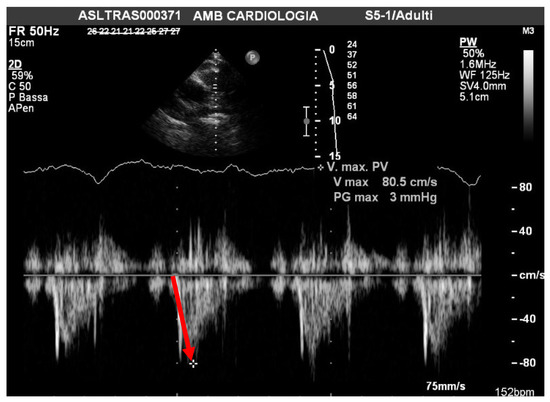

| PAAT | acceleration time of pulmonary outflow |

| sPAP/PAAT ratio | systolic pulmonary artery pressure/acceleration time of pulmonary outflow ratio |

| Mean PAAT 110 msc |

| sPAP/PAAT 0.26 |

| Mean sPAP/PAAT 79.7 ± 7 |

| sPAP/PAAT 0.4 |